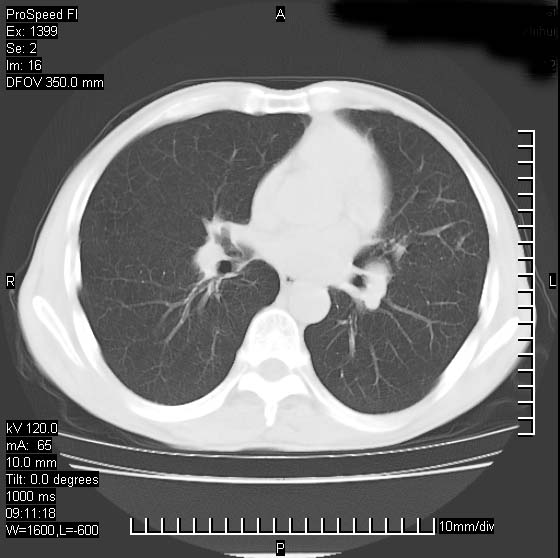

以下是引用卜一在2007-1-19 9:55:00的发言:[br]左肺沿胸膜下巨大肿块影,边缘呈分叶征,纵隔内见肿大淋巴结,右肺内另见一不规则结节影 .考虑:左肺周围性肺癌伴纵隔 右肺内转移.

以下是引用rgsyyf在2007-1-19 11:05:00的发言:[br]左肺上叶见形态不规则巨大软组织肿块影,边缘呈分叶征,纵隔内隆突下见肿大淋巴结,右肺内另见一不规则结节影 .考虑:左肺周围性肺癌伴纵隔即右肺内转移.